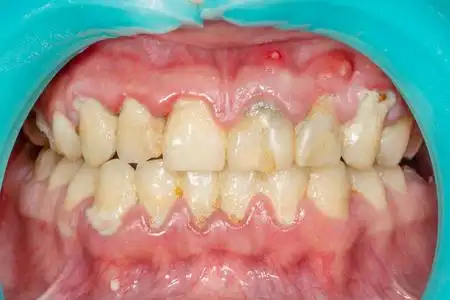

牙结石,俗称牙垢,是硬化的斑块.在下图中,牙垢看起来像一

病人结石的斑块. 牙科治疗牙菌斑专业口腔卫生.